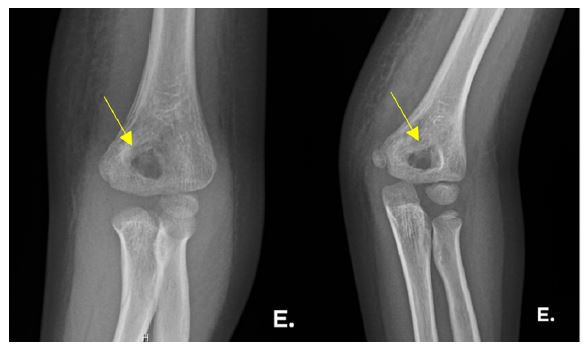

On admission, she presented in an antalgic position with semi-flexed left elbow with marked edema and slight thermal asymmetry without local flushing. Blood analysis revealed mild anemia (hemoglobin 10.3 g/dL) and neutropenia (neutrophils 1010/uL) and elevated inflammatory parameters (ESR 55 mm/1sth; CRP 46.8 mg/L). Ultrasound of the left elbow showed a joint effusion, radiography showed a periosteal reaction in the left distal humerus (Figure 2), and Tc99m scintigraphy showed an osteoblastic lesion centered on the distal end of the left humerus (Figure 3). The diagnosis of septic arthritis/osteomyelitis was established. Arthrocentesis and arthrotomy were performed with extensive washing of the elbow, and intravenous antibiotic therapy with flucloxacillin was started. Synovial fluid cytology showed 85% polymorphonuclear leukocytes. There was improvement, with resolution of symptoms and no limitation of elbow mobility. Blood and synovial fluid cultures were negative, inflammatory parameters improved, and anemia resolved. The girl was discharged asymptomatic after 11 days of oral antibiotic therapy (amoxicillin) and was referred for outpatient Orthopedic and Hematology consultations due to worsening neutropenia (min 350/uL neutrophils). Constitutional neutropenia or post-infectious neutropenia was hypothesized, but the study revealed a normal peripheral blood smear, normal peripheral blood immunophenotyping with no circulating immature cells or abnormal lymphocyte subsets, normal % fetal haemoglobin (HbF), normal serum immunoglobulins, no detectable direct anti-neutrophil antibodies (IgG/IgM) on flow cytometry, and a normal next-generation sequencing (NGS) panel for congenital neutropenia genes.

Bone involvement in ALL can be translated radiologically into osteolytic lesions, metaphyseal bands, decreased bone density, osteosclerosis, pathologic fractures, and periosteal reactions.11,16 These and other changes may occur in 41-75% of children with ALL.10,12,13) Brix et al. reported changes in 61% of children who underwent osteoarticular scintigraphy, although it has limited diagnostic value in these situations.14 The alterations on scintigraphy were also confounding factors in both cases presented.